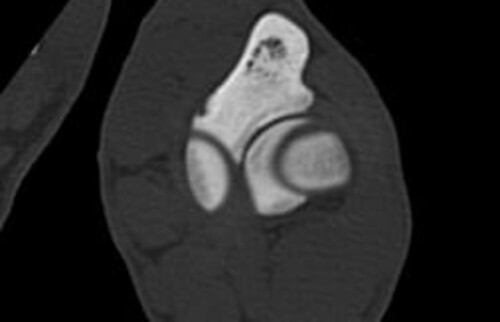

Nach der klinischen Diagnose werden die Hunde in unserer Klinik direkt im Computertomografen untersucht, sodass genau beurteilt werden kann, welche Gelenksanteile wie schwer betroffen sind, um eine individuelle Therapie festzulegen.

Schwarz-weiss Röntgenaufnahme